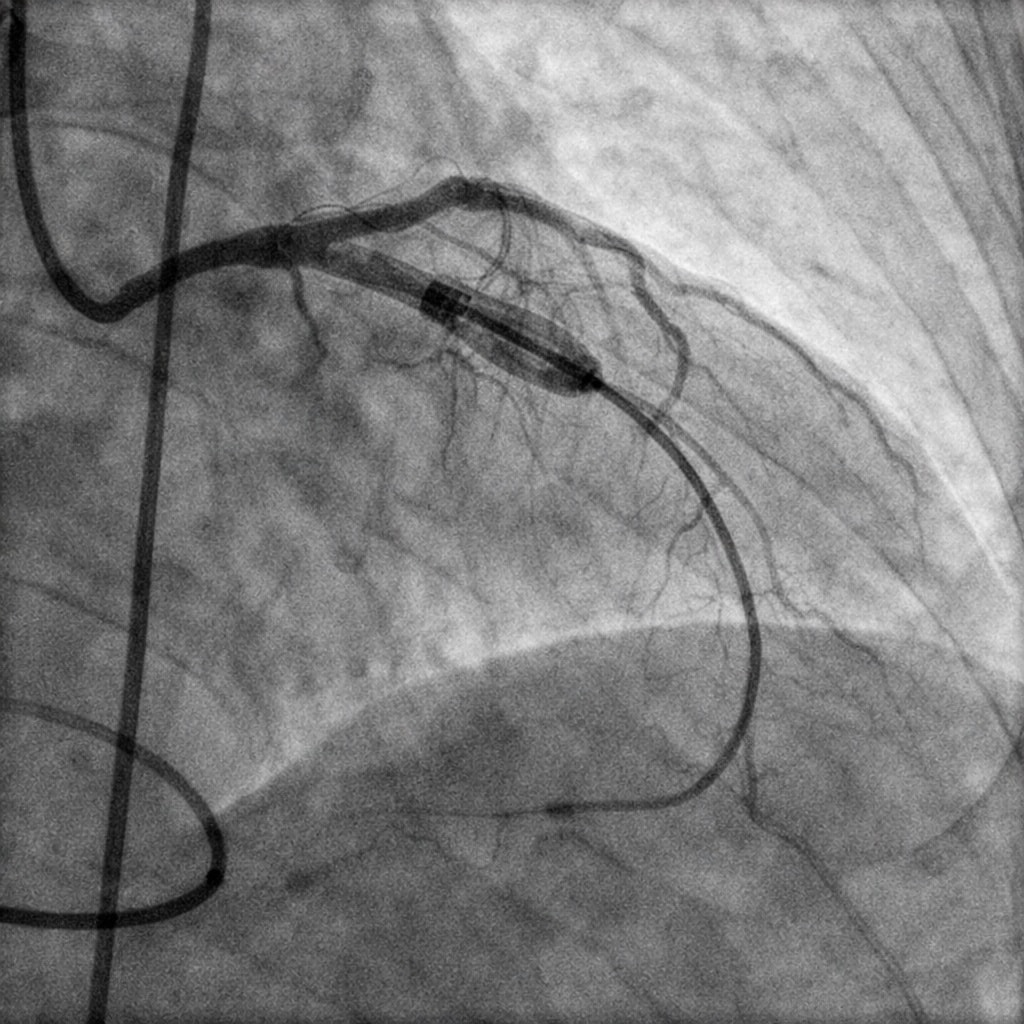

تم تشخيص إيهاب بسرعة وعمل له قسطرة وتركيب دعامة، لكن بعد أسبوع واحد فقط بدأت تظهر علامات ضعف عضلة القلب، أصبح يعاني من نهجان شديد مع أقل مجهود، كحة مستمرة وشرقة توقظه من النوم، وفحوصات القلب أظهرت كفاءة منخفضة للقلب بنسبة 30% مع ارتجاع في الصمام الميترالي وارتفاع ضغط الشريان الرئوي.